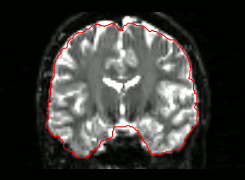

07 Masking

DWI

Quality Assessment

- One task - one QA

- General summary

- Global information

- Visual output

- Easy interface web-based